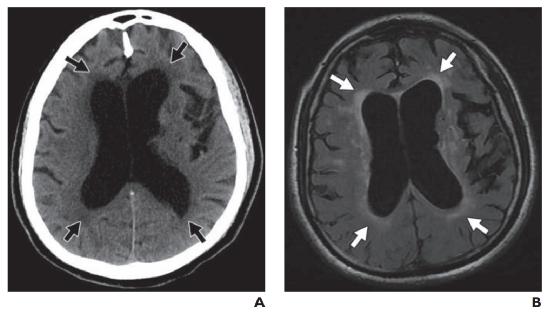

3.间质性水肿

间质性(脑积水)水肿发生在脑室内压升高的情况下,这会导致脑室室管膜内层破裂。这允许脑脊液经室管膜迁移到细胞外空间,最常见的是脑室周围白质。液体成分与 CSF 相同,具有相似的离子浓度和可忽略不计的蛋白质(与血管源性水肿相反)。间质性水肿的各种原因包括阻塞性肿块、脑膜炎、蛛网膜下腔出血和正常压力脑积水。相比之下,颗粒性室管膜炎是指前外侧额角周围的小三角形异常信号区域(图 11 )). 这种正常的解剖变异是由于局部髓鞘减少、细胞外液增加或室管膜内层局部破裂伴神经胶质增生所致。在 CT 上,脑室扩大和脑室周围低密度增加的组合提示间质性水肿的诊断(图 12A )). MRI 是一种更敏感的成像方式,在 T1 加权成像上显示低信号,在 T2 加权成像/FLAIR 上显示脑室周围高信号(图 12B )). 脑室周围高信号可根据其严重程度分级。1 级(不连续)表现为靠近额角和枕角以及侧脑室的局灶性信号异常。2 级和 3 级(连续和脑室周围晕)完全围绕脑室并且厚度不同。4 级(弥漫性白质异常)延伸至灰白质交界处。由于水肿位于细胞外,DTI 图可能显示局部各向异性分数降低。然而,平均总体扩散率在 DWI 和 ADC 图上是正常的。

图12—正常压力脑积水。A,未增强的CT图像显示明显的侧脑室扩大,与脑沟不成比例。额角和枕角周围的低密度(箭头)反映了脑脊液跨室管膜的迁移。B,FLAIR磁共振图像再次显示脑室扩张和1级室周高信号(箭头)。也存在微血管疾病的分散病灶。